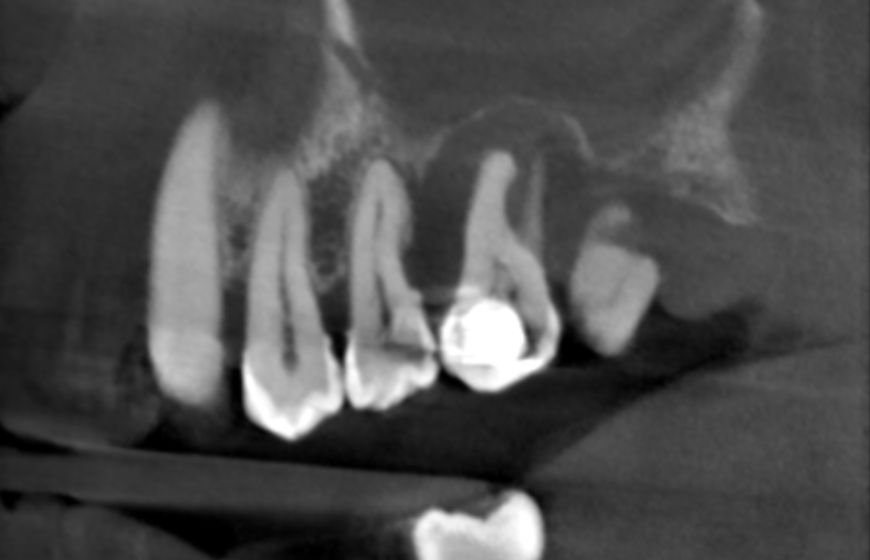

Diagnostyka zgorzeli zęba opiera się na badaniu klinicznym oraz zdjęciach RTG. RTG umożliwia dentystom ocenę stanu miazgi oraz tkanek otaczających ząb. Na zdjęciu RTG lekarz może zidentyfikować zmiany w strukturze kości wokół korzenia zęba, co wskazuje na infekcję.

Tomografia komputerowa czyli badanie CBCT 3D mogą być stosowane w diagnostyce zgorzeli zęba, aby uzyskać lepszy obraz tkanek. Regularne kontrole RTG są ważne dla monitorowania postępu leczenia zgorzeli zęba. Dokładna diagnostyka zgorzeli zęba pozwala na precyzyjne określenie stopnia zaawansowania infekcji.